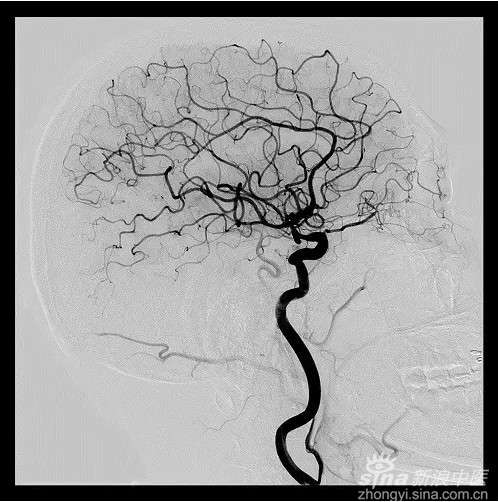

DSA,是通过计算机把血管造影片上的骨与软组织影像消除,仅在影像片上突出血管的一种摄影技术。

DSA不但能清楚地显示颈内动脉、椎基底动脉、颅内大血管及大脑半球的血管图像,还可测定动脉血流量,所以,被广泛应用于脑血管病检查,特别是对于动脉瘤、动静脉畸形等定性定位诊断,更是最佳的诊断手段。对病变的范围及严重程度,亦可清楚地了解,为手术提供较可靠的客观依据。

2016年9月13日,同济赤壁医院成功开展一例脑血管介入造影术,这又一次凸显了介入诊疗手术微创、高效不可替代的临床价值。

患者及家属得知同济赤壁医院设备先进,并长期有武汉同济总院专家坐诊,便前来就诊。患者入住同济赤壁医院神经内科后经介入科会诊,于9月13日行脑血管介入造影术,进一步确诊为颅内动脉多发硬化狭窄、右侧大脑后交通动脉小型动脉瘤,为后期有效治疗指明了方向,得到患者与家属好评。